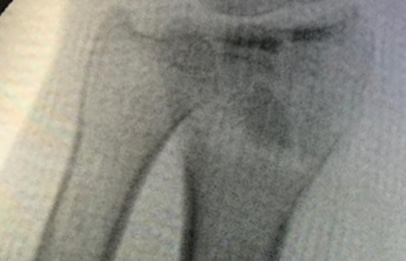

Cirugía de Fémur - Cirugías de Muñecas y Manos

Los procedimientos más comunes en cirugía de la mano son aquellos destinados a reparar traumatismos, incluyendo lesiones de tendones, nervios, vasos sanguíneos, y articulaciones; huesos fracturados; y quemaduras, cortes, y otros daños de la piel.